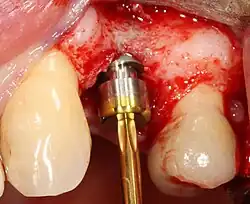

Placing the implant

Most implant systems have five basic steps for placement of each implant:[14]: 214–221

- Soft tissue reflection: An incision is made over the crest of bone, splitting the thicker attached gingiva roughly in half so that the final implant will have a thick band of tissue around it. The edges of tissue, each referred to as a flap, are pushed back to expose the bone. Flapless surgery is an alternate technique, where a small punch of tissue (the diameter of the implant) is removed for implant placement rather than raising flaps.

- Drilling at high speed: After reflecting the soft tissue, and using a surgical guide or stent as necessary, pilot holes are placed with precision drills at highly regulated speed to prevent burning or pressure necrosis of the bone.

- Drilling at low speed: The pilot hole is expanded by using progressively wider drills (typically between three and seven successive drilling steps, depending on implant width and length). Care is taken not to damage the osteoblast or bone cells by overheating. A cooling saline or water spray keeps the temperature low.

- Placement of the implant: The implant screw is placed and can be self-tapping;[31]: 100–102 otherwise, the prepared site is tapped with an implant analog. It is then screwed into place with a torque controlled wrench[35] at a precise torque so as not to overload the surrounding bone (overloaded bone can die, a condition called osteonecrosis, which may lead to failure of the implant to fully integrate or bond with the jawbone).

- Tissue adaptation: The gingiva is adapted around the entire implant to provide a thick band of healthy tissue around the healing abutment. In contrast, an implant can be "buried", where the top of the implant is sealed with a cover screw and the tissue is closed to completely cover it. A second procedure would then be required to uncover the implant at a later date.